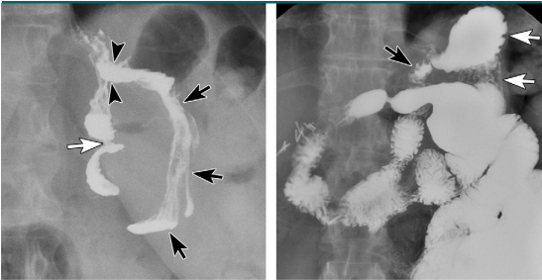

Crohn’s

Multiple aphthous (superficial) erosions are present on the antrum. Duodenal folds are thick and nodular (cobblestone mucosa).

benign or malignant?

benign

malignant ulcer with a carmen meniscus sign